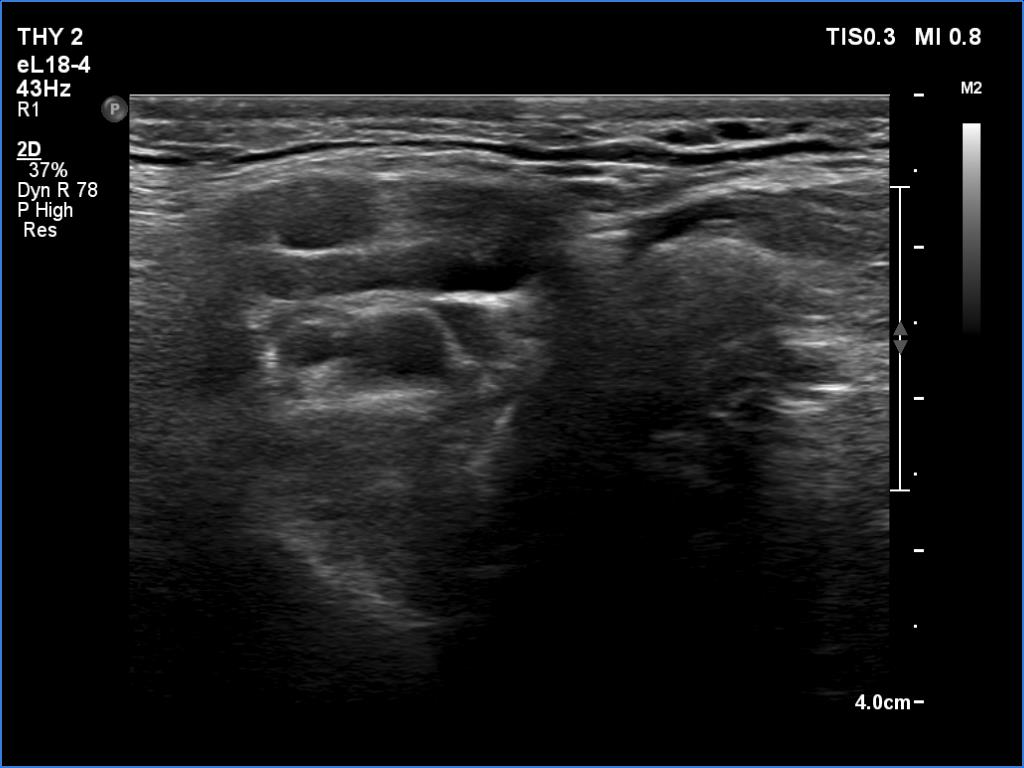

Follow-up examination 8 years later (4th and 5th rows of images):

Clinical data: The patient was referred for evaluation of a continuously increasing thyroglobulin level which resulted in 2.86 ng/mL, 5.74 ng/mL and 20.1 ng/mL, at the 2-yr, 5-yr and 7-yr follow up. Cytology of enlarged lymph nodes, multiple CT-scans and PET-CTs failed to reveal recurrence.

Palpation: There were two palpable, firm but freely moveable masses in the right and left submandibular area.

Hormonal examination: indicated euthyroidism with TSH 2.95 mIU/l on daily 125 microgram levothyroxine. Thyroglobulin was 15.4 ng/mL, anti-hTg was below 20 U/mL.

Ultrasonography revealed hypoechoic discrete lesions in both thyroid lobes. The lesions presented microcalcifications. Corresponding to the palpable mass in the right submandibular region, a reactive-type regular lymph node was found. There was an enlarged lymph node in the left submandibular region. The node had a regular hilum but displayed a heterogeneous pattern.

Cytology was performed from both lymph nodes and from the lesion in the left thyroid bed. FNA resulted in non-diagnostic report from the lesion in the left thyroid bed while cytology of the submandibular lymph nodes showed patterns of a benign, reactive-type lymph node.

Wash-out thyroglobulin levels were 0, 81.1 and 104.9 ng/mL, right submandibular lymph node, left thyroid bed lesion and left submandibular lymph node, respectively.